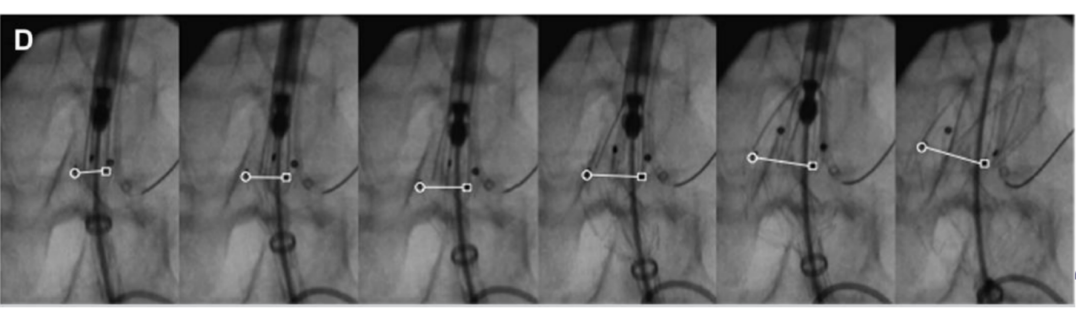

支架即时下移的风险和控制

文献报道,支架移位较Ⅰ型内漏在随访过程中可能出现更多并发症。即时下移只有2毫米左右,如果不掌控其原因,也可能导致严重内漏。即时下移需要加以重视,并严密控制。

可能导致垂直作用力过大,从而引起支架上移。释放过程中MARK点漂移是OVERSIZE过大的征象,表现为支架受到挤压为主,导致MARK先升后降。

不规则瘤颈的影响

会影响瘤颈-支架之间的相互作用力的均衡,留下更多空余空间,造成内漏。瘤颈成角和梯形形态会个体化地影响瘤颈长度和相互作用力;瘤颈扭曲导致相互作用力不充分均衡,支架第一节和第二节的间隙因贴壁不牢被血流冲击导致堆叠是其下移主要原因。